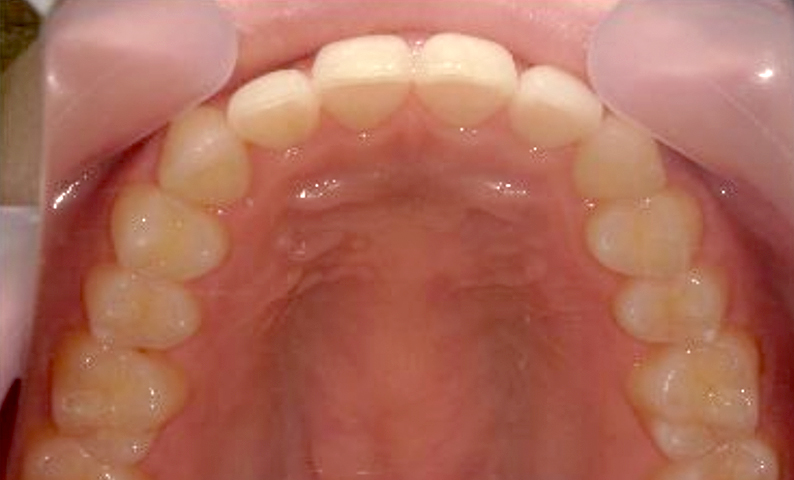

| 治療前 | 治療後 |

|---|---|

|